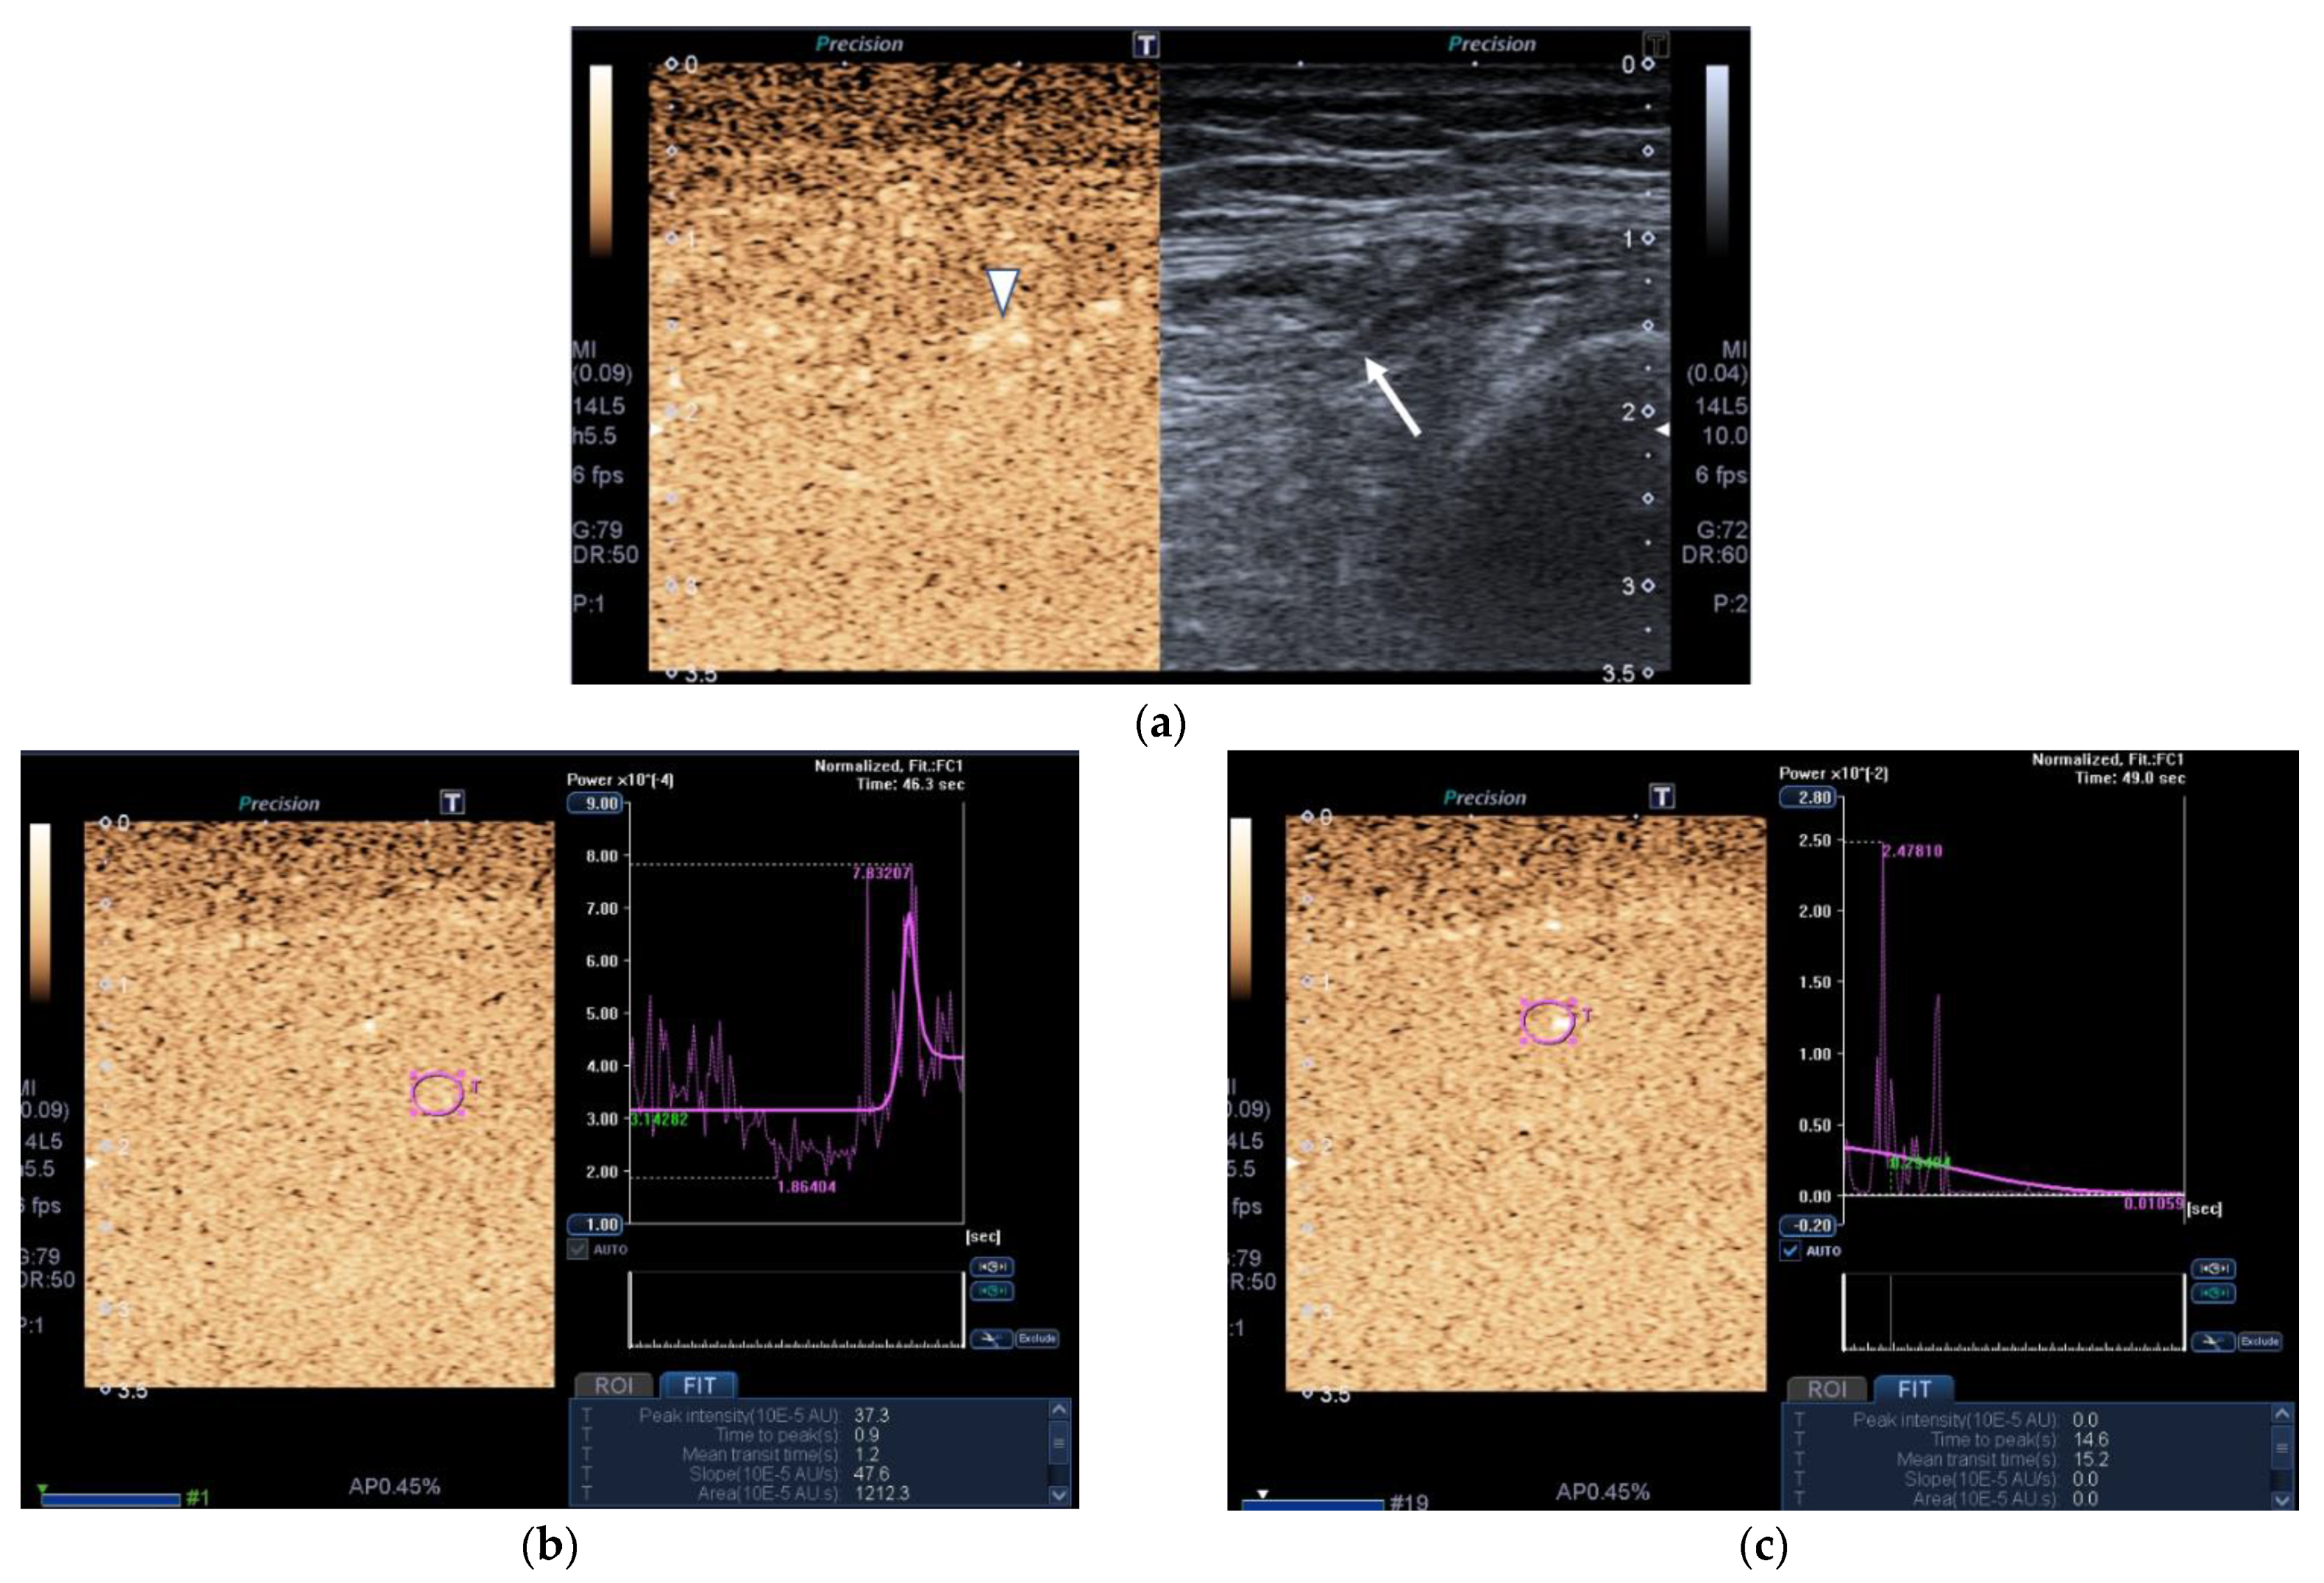

Figure 4.

Transversal QRF muscle of a patient with multiorgan failure (77 years old). (a). Transversal ultrasonography scan shows the QRF muscle (arrow) and vascularization after contrast-enhanced ultrasound (CEUS) administration (arrowhead). CEUS imaging and time–intensity curve analysis are shown using the built-in software. (b) ROI (pink circle) in the area of strongest enhancement indicates maximum perfusion in the QRF. (c) ROI (pink circle) in the area of lowest enhancement indicates minimum perfusion in the QRF.

Images of the peak maximum and minimum CEUS intensity of a patient and a healthy control are shown in Figure 3 and Figure 4.